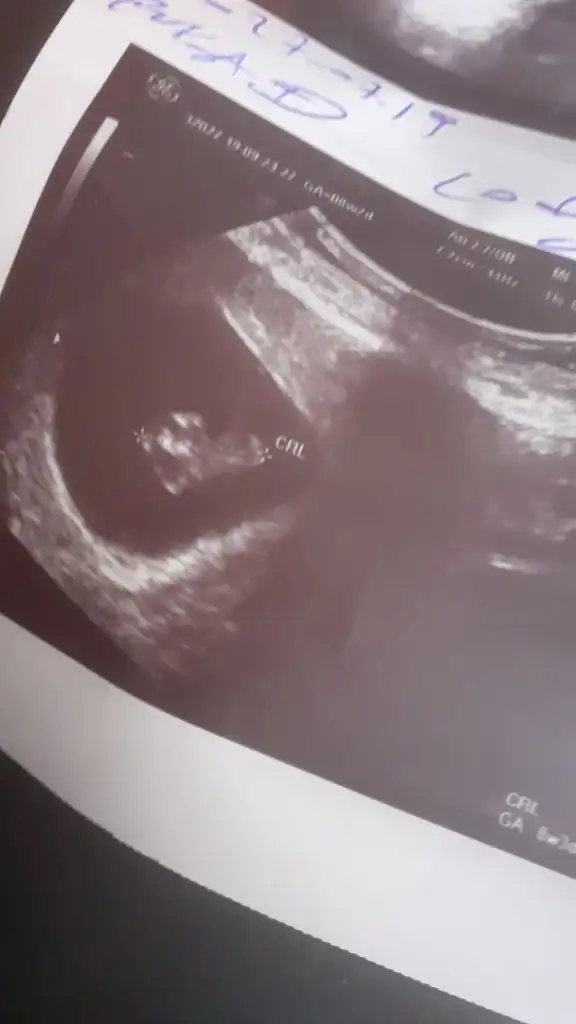

Buna göre kızEki Görüntüle 2309620 Bana da yorum yapar mısınız acabavajinal ultrason

6 yada 7 hafta olmalı